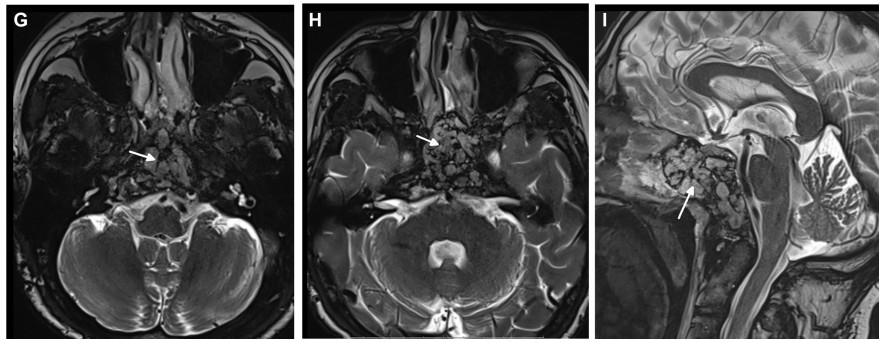

▼术后MRI证实肿瘤完全切除,显示用于术后残腔重建填充的脂肪(白色箭头表示脂肪移植)。

术后MRI证实肿瘤完全切除,无脑水肿和脑出血。术后2月随访,内镜检查没有发现结痂,患者也没有抱怨任何鼻腔不适。